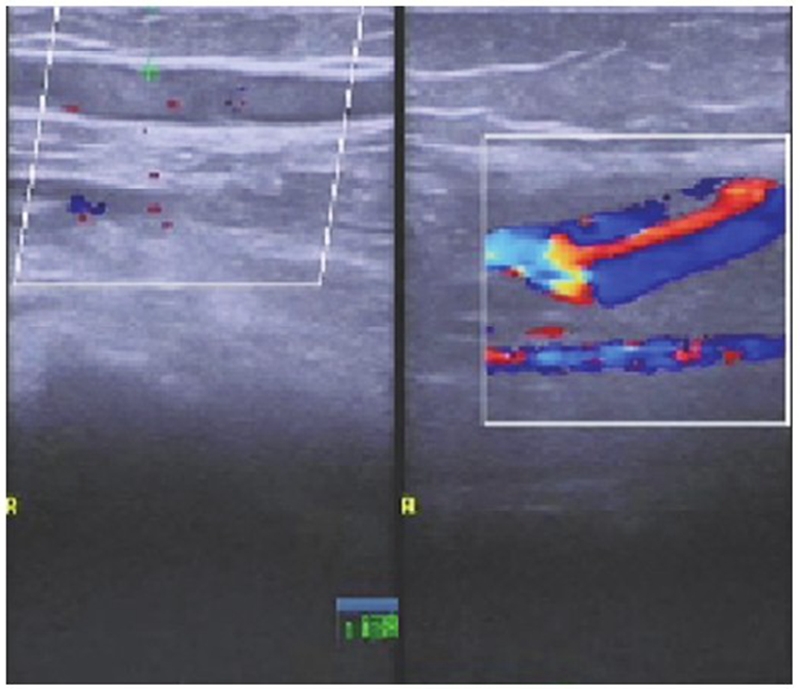

术后第1天复查下肢血管彩超及实验室检查凝血功能,发现腘动脉血栓形成及凝血功能异常(图4~5),患者未诉 不适。体检发现足背动脉搏动较对侧弱,皮温略低,末梢血氧饱和度90%。请显微外科及心血管内科会诊后,心血管内科建议切开取栓,将病情告知患者及家属后行急诊取栓术。术中可见腘动脉分叉近端约2cm大小的半月板缝合袢将腘动脉捆扎,但仍有血流通过(图6),切开血管,取出血栓,取出半月板缝合袢,松开止血带,见血流好,在显微镜下修复腘动脉,再次松开止血带,见动脉搏动良好,无漏血,足背动脉搏动好,末梢血氧饱和度99%,手术完毕。患者术后第1天开始主动活动,双侧皮温一致,未诉患肢疼痛,复查右下肢动静脉彩超示右侧动静脉血流通畅(图7),术后24个月随访患者右下肢活动功能良好,双下肢无明显肿胀,双侧皮温一致,小腿腿围基本一致,患者McMurray征阴性,前抽屉试验阴性,膝关节稳定性良好,活动度良好。

图7 右侧腘窝处皮下血管内低回声点提示浅表静脉早期血栓形成